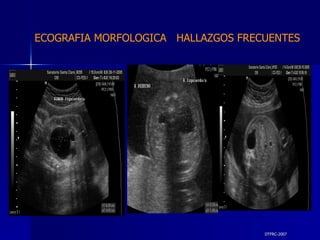

DTFRC-2007 ECOGRAFIA MORFOLOGICA  HALLAZGOS FRECUENTES   SISTEMA NERVIOSO CENTRAL TOTAL  8  26 % 1 HIDROCEFALIA 2 VENTRICULO MEGALIA 4 QUISTE DE PLEXO COROIDEO 1 ANENCEFALIA

DTFRC-2007 ECOGRAFIA MORFOLOGICA  HALLAZGOS FRECUENTES   GENITOURINARIA DISPLASIA RENAL MULTIQUISTICA  3 HIDRONEFROSIS  2 QUISTE DE OVARIO FETAL  1 SISTEMA DIGESTIVO DILATACION INTESTINAL  2  SISTEMA ESQUELETICO   PIE BOT  2  20 % 6 % 6 %